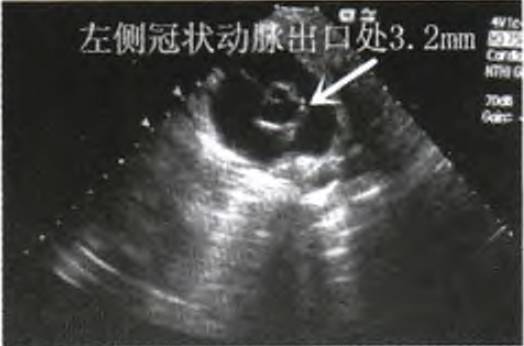

入院后予氨曲南抗感染,甘草酸二铵营养肝功能。患儿仍反复高热,咽部充血明显,双侧扁桃体I度肿大,右侧扁桃体可见白色块状分泌物,双侧颈部可扪及肿大淋巴结,脾脏肿大,伴肝功能损害,结合白细胞计数及淋巴细胞数较入院前明显升高,需警惕EB病毒感染,急查EB病毒抗体。患儿仍高热,双结膜充血,颈部可扪及肿大淋巴结,双足背及趾端稍肿胀,不能除外川崎病,行心脏彩超检查,结果回报:左侧冠状动脉出口处3.2 mm,右侧冠状动脉出口处4.5 mm(图1),患儿冠状动脉扩张明显。

图1 患儿入院次日心脏彩超左、右侧冠状动脉扩张改变

患儿入院次日心脏彩超检查结果示左侧冠状动脉出口处3.2 mm,右侧冠状动脉出口处4.5mm,根据冠脉扩张性病变诊断标准,双侧冠状动脉均扩张,右侧明显,虽患儿无口唇潮红、皲裂,无杨梅舌,无掌、跖面潮红,但结合患儿反复高热,双结膜充血,颈部可及肿大淋巴结,双足背及趾端稍肿胀,考虑不完全川崎病(Kawasaki disease,KD),给予丙种球蛋白联合阿司匹林治疗。